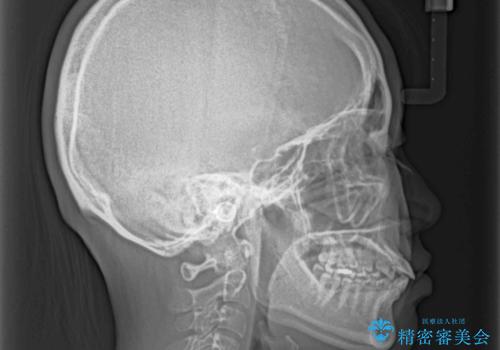

- 歯の欠損による隙間だらけの歯並びを気にして来院された患者様です。

上顎左右1本ずつ欠損していたため、歯列矯正により欠損部位にスペースを集め、その後欠損部位をインプラントにて補綴することとしました。

インビザラインによる矯正治療も提案しましたが、長時間の装着や自己管理が難しいとお考えで、ワイヤーによる矯正治療を行いました。

歯並びは比較的早めに整いましたが、インプラントを埋入するにあたって前後の歯根位置を改善する必要があり、矯正治療に期間を要することとなりました。